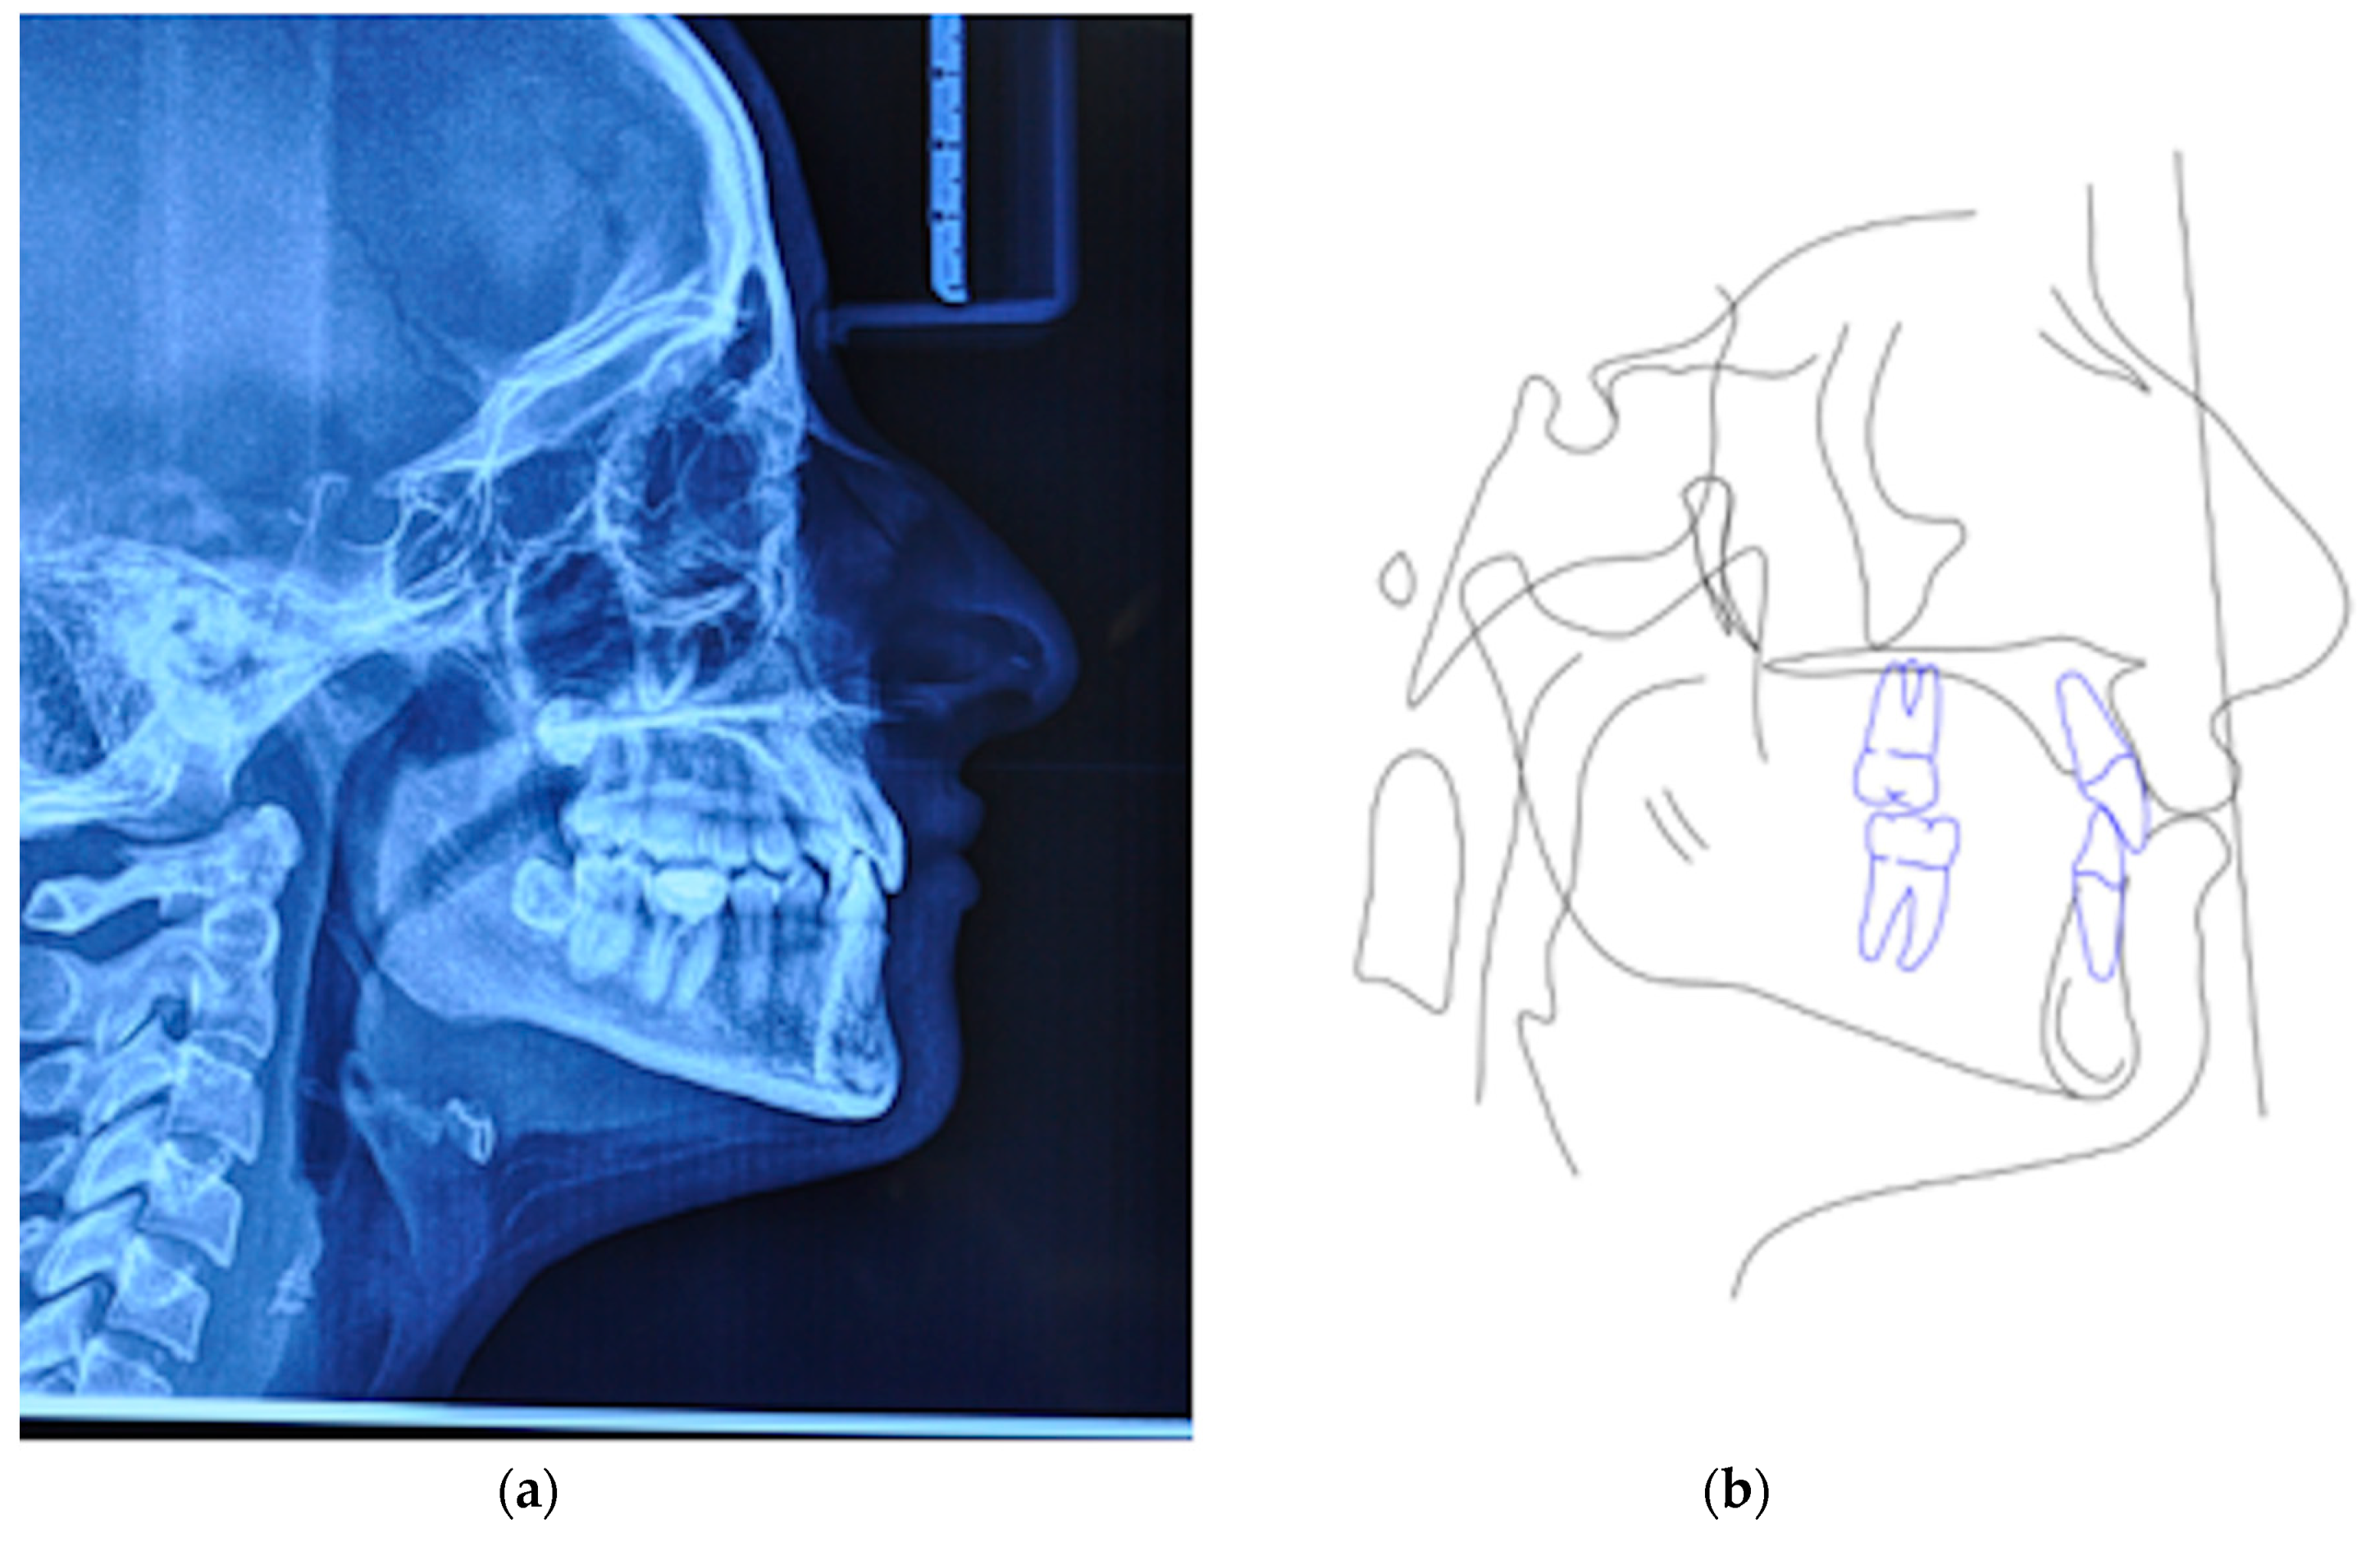

A 25 years old female attended consultation for orthodontic treatment to enhance the aesthetic of the smile. In particular, the chief complain was the crowded teeth along with the presence of wide buccal corridors while smiling. Facial analysis revealed retrognatic profile with labial competence, no gingival exposure during smiling along with extensive buccal corridors (Figure 7a–c). Intra-oral examination revealed class I molar and canine relationships, significant maxillary and mandibular crowding, mild maxillary transversal deficiency with cross-bite on the right side due to mandibular shift toward cross-bite side, significant anterior overbite (Figure 8a–e). Panoramic examination showed healthy condition of the upper first molars that would support the dental anchorage of the MSE device (Figure 9). Cephalometric analysis (Figure 10a,b) confirmed that the patient presented skeletal class I maxillo-mandibular relationship with retruded profile, mesiofacial growth pattern and anterior overbite. Patient approved the usage of photographic and radiographic records for the purpose of publication, by signing a specific form.

Figure 10.

(a) Lateral cephalogram, (b) pre-treatment cephalometric tracing.